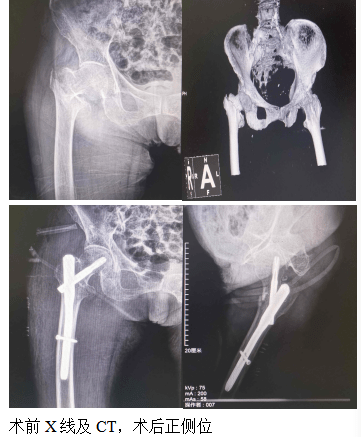

让老年患者告别“最后一次骨折” 海北州二院创伤中心进入微创时代仔细查体并结合患者影像记录制定手术方案,与当地医生交流讨论、充分评估手术风险、取得患者及家属同意后,制订了微创治疗闭合复位PFN... 在微创治疗出现前,业内常称该处骨折为“老年人的最后一次骨折”。随着生活水平的提高,超高龄股骨粗隆间骨折患者逐渐增加,如何提高围术...